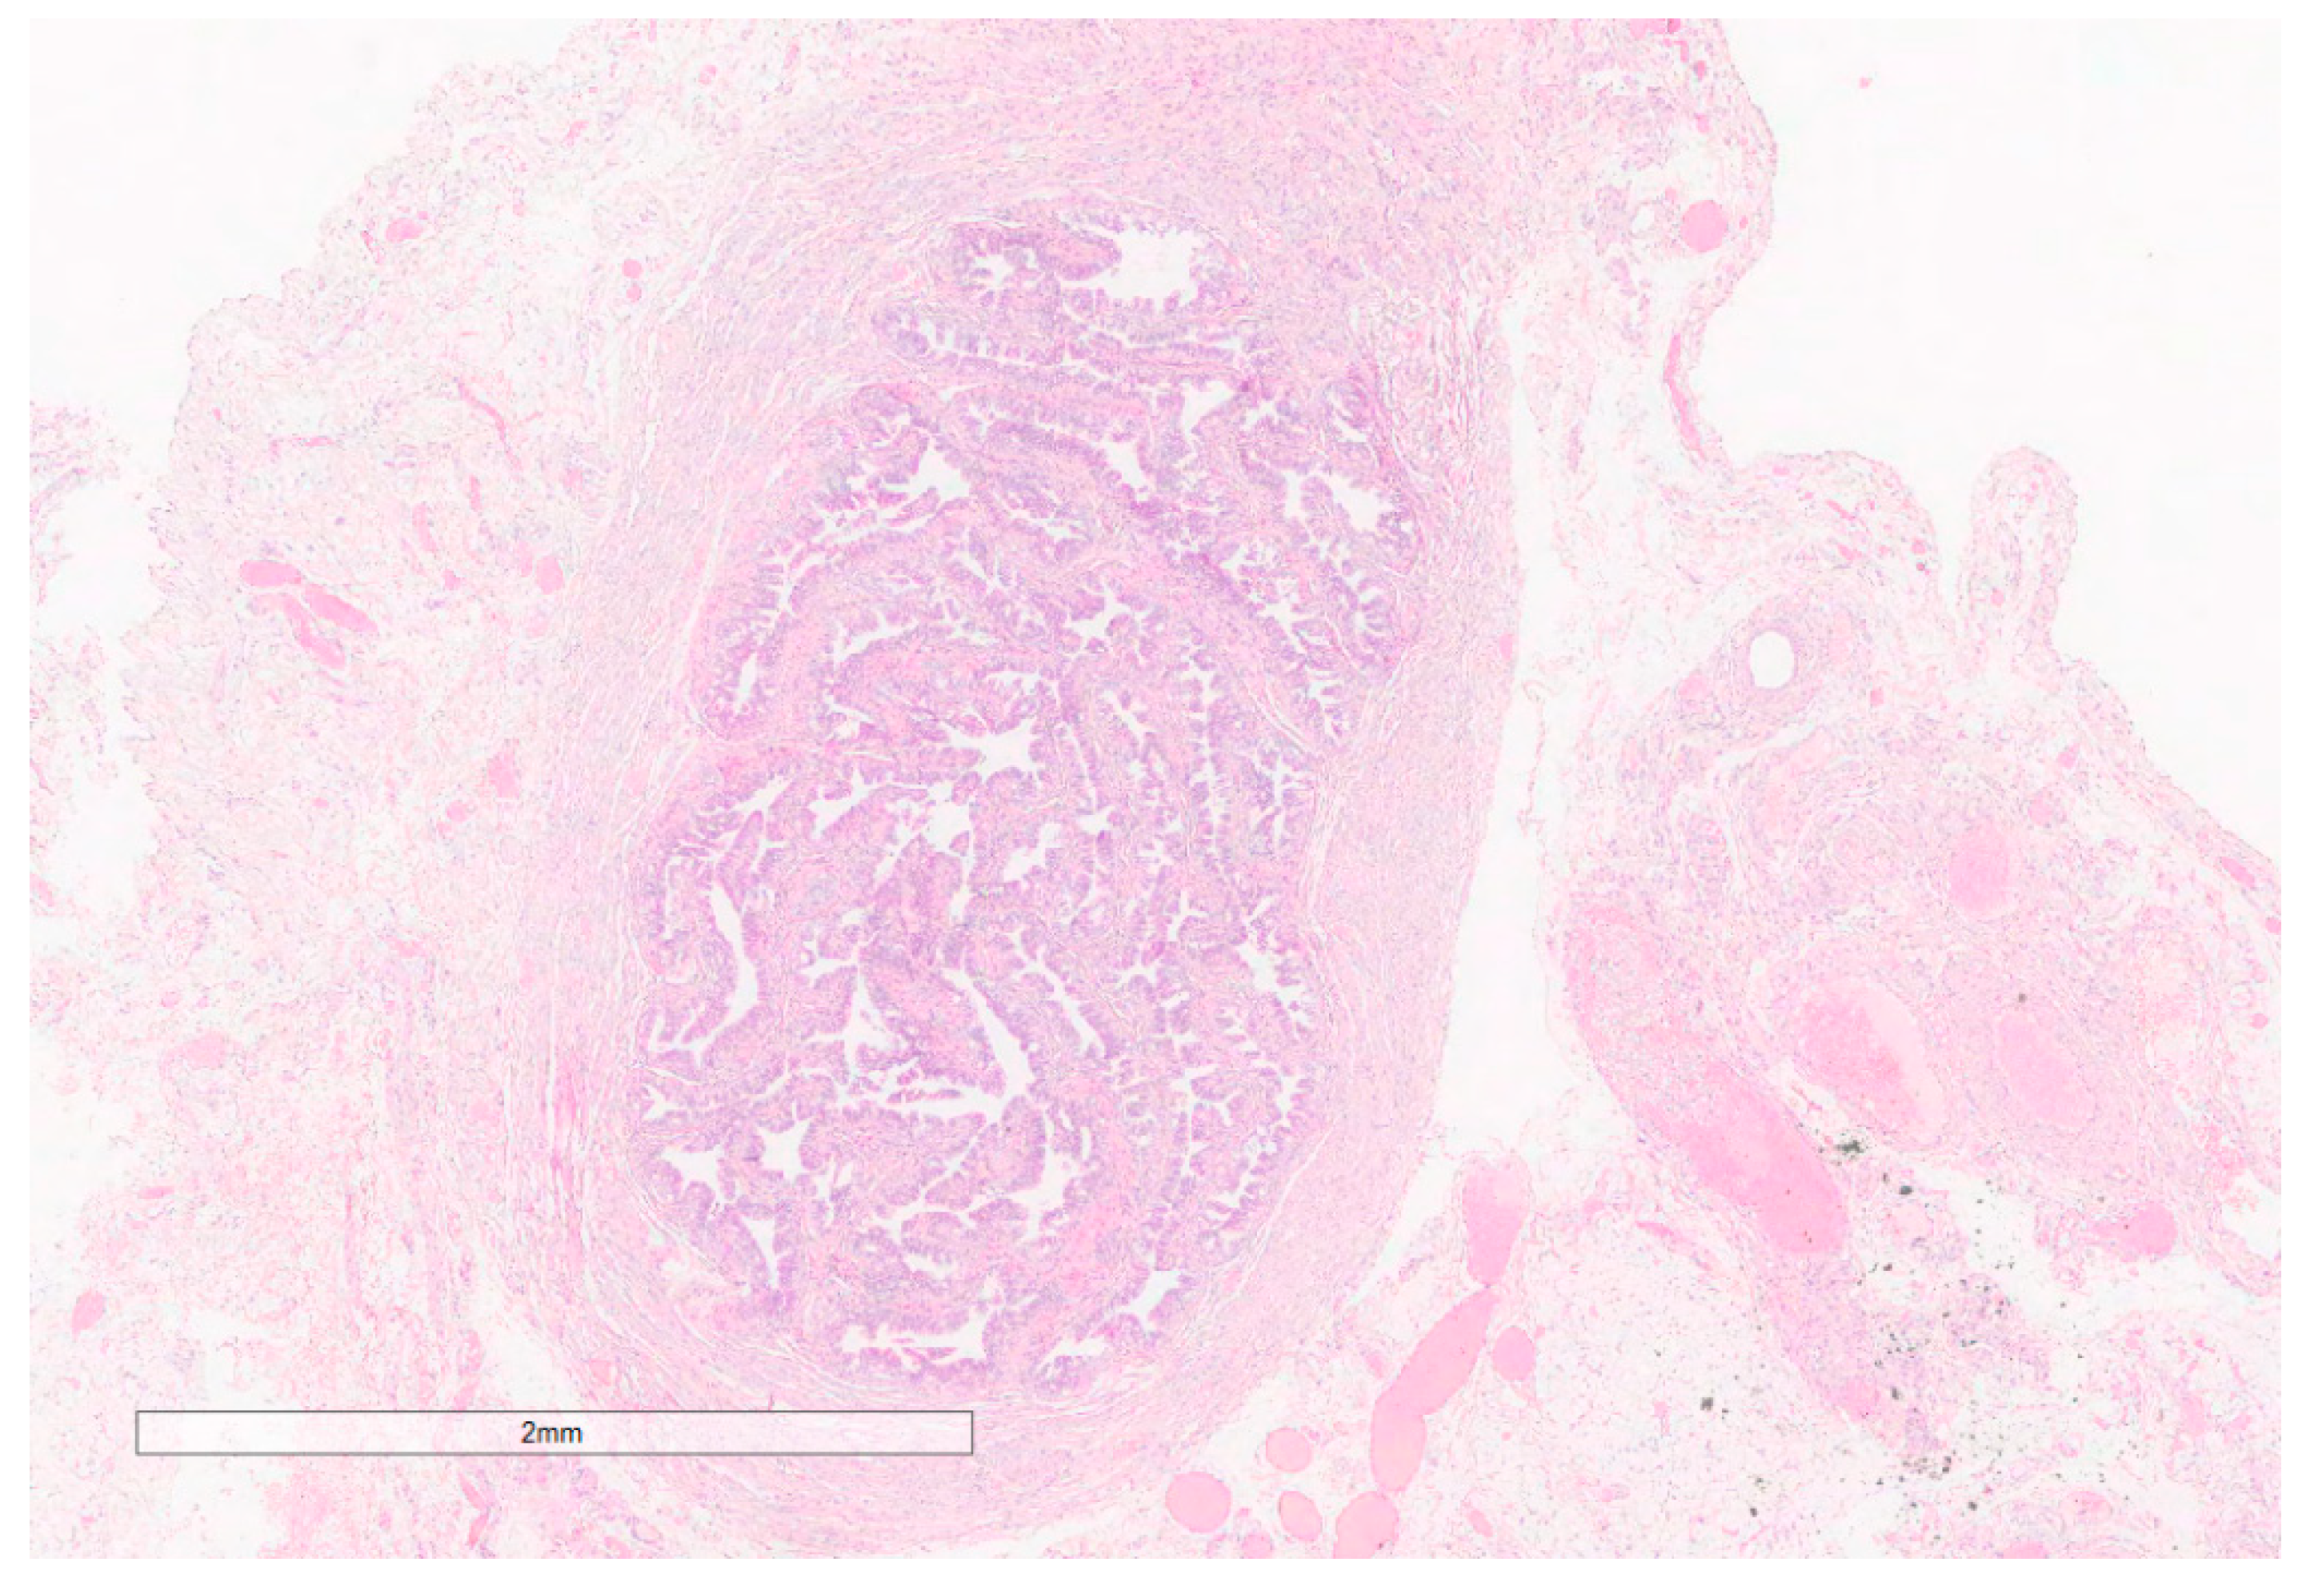

| 1 (Our case) | BG(Ls) | NR | SCA + SCH + SLCT | M | B (SCA, SCH) L (SLCT) | 1.8 |